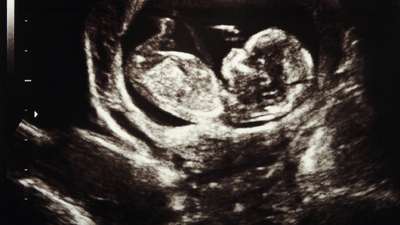

Gebelikte sigara içiminin erken doğum, gebelik kayıpları, bebekte gelişme geriliği, düşük doğum ağırlığı ve ani bebek ölümlerine neden olduğunu aktaran Erdöl, anne, gebelikte sigara içimini bıraktığında bu sonuçlarda önemli bir iyileşme olduğunu dile getirdi

Erdöl, nikotinin bebeğin beyninde morfolojik ve fonksiyonel değişiklikler oluşturduğunu belirterek şunları kaydetti: "Gebelikte sigara içen annelerin çocuklarında dil öğrenmede zorluklar, düşük IQ, anksiyete, dikkat eksikliği ve hiperaktivite sendromu bildirilmiştir. Annenin günlük içtiği sigara sayısı arttıkça dikkat eksikliği ve hiperaktivite sendromunun şiddeti de artmaktadır. Gebelikte sigara içimi bebekte metabolik bozukluklara da yol açmakta, obezite, diyabet ve hipertansiyon riskini artırmaktadır. Bu çocuklarda solunum yolu hastalıkları da artmakta, alt ve üst solunum yolu enfeksiyonları, bronşit, astım daha sık izlenmektedir. Akciğerler anne karnında gelişim evresinde nikotine maruz kaldığında akciğer hacmi ve büyüklüğü kısıtlanmakta, oksijen alımının sağlandığı alveolar yüzey azalmaktadır."

Erdöl, anne karnındaki bebek nikotine maruz kaldığında beyin tümörü, lösemi ve lenfoma riskinin arttığını, çocuklarda tümör gelişimine yol açtığını bildirdi.